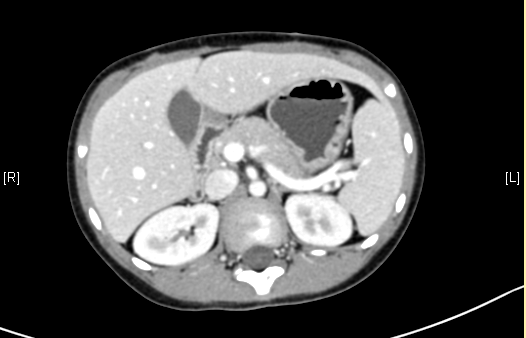

术前CT检查:

平衡期

一般情况:CH-001-LT-000009,男,7岁,身高128cm,体重24.5kg。

现病史:因感冒后出现上腹部不适,至当地医院就诊,查腹部超声示“肝脏占位”,遂至青岛妇女儿童医院就诊,查腹部CT示“肝脏占位”,未予特殊治疗,为求进一步诊治来我院就诊,门诊以"肝脏占位"收入院。

腹部超声示:肝内包块。腹部CT:肝脏占位,血管瘤?上腹部增强CT:肝左内叶-右前叶交界区、尾叶囊实性团块影,考虑肿瘤(胆管囊腺瘤?间叶性错构瘤?)